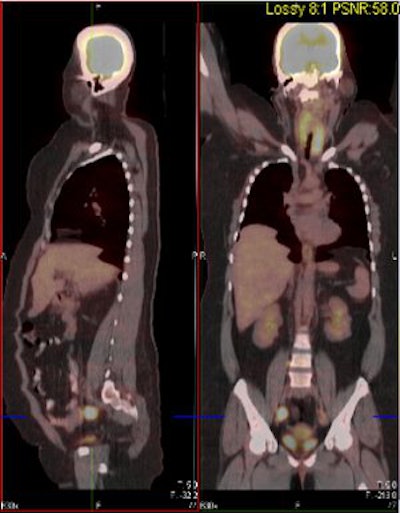

| Above and below, representative images of a 39-year-old patient, currently undergoing treatment, with FIGO stage IB2 squamous cell carcinoma of the cervix. Pretreatment FDG-PET/CT identified an FDG-avid cervical tumor mass plus bilateral iliac and right common iliac metastatic lymphadenopathy. Images courtesy of Dr. Julie Schwarz, Ph.D. |